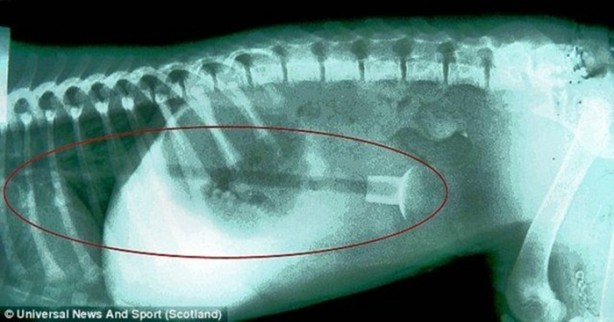

Bu yaramazın adı Betty...

Staffordshire bull terrier cinsi olan bebek Betty, her meraklı yavru köpek gibi bulduğu cisimleri çiğneme hevesinin kurbanı olmak üzereyken kurtarıldı.

Zira kendisi tam 25 cm'lik bir oyuncak ok yutmuştu. Yutuğu oyuncak başarılı bir operasyonla alındı ve Betty sağlığına kavuştu.